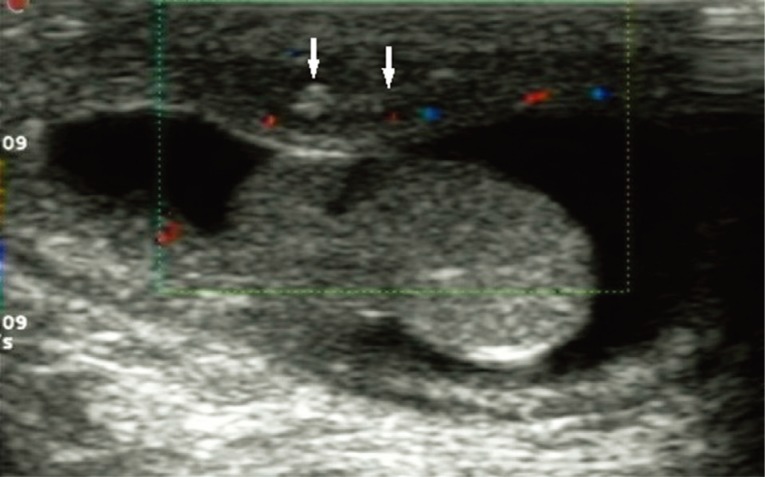

A 5-month-old boy was found to have an asymptomatic left scrotal mass for 3 months. The mass was soft, non-tender and without overlying scrotal skin abnormality. Ultrasound examination identified that the left scrotal wall was thickened with a mixed-echogenicity mass measuring 11×3 mm, which had an obscure boundary and increased blood supply on color Doppler (Fig. 1). The mass was thought to be inflammatory in origin, and observation was recommended. However, repeat ultrasound examinations demonstrated the mass to be increasing in size. The last ultrasound examination revealed a 19×9 mm hetero-echogenic mass with ill-defined margins. Physical examination demonstrated a flat mass of the left scrotum measuring 20×10×3 mm, with non-homogeneous consistency, ill-defined borders and no tenderness. CT showed a mass of 12×9 mm anterior to the left testicle, with heterogeneous density and punctate calcifications (Fig. 2A) and obvious enhancement after administration of contrast agent (Fig. 2B), which was diagnosed as a left testicular teratoma. The complete blood count (CBC), electrolytes, and liver function tests were all normal prior to surgery. The eosinophil differential count was 6% (normal range: 0.5 to 5%). No parasite eggs were found on routine stool testing. The α-fetoprotein (AFP), 19.5 µg/L (normal <20 µg/L), and human chorionic gonadotropin (HCG), 2.01 µg/L (normal <3.1 µg/L), were both normal.

Ultrasound is often used for evaluation of superficial subcutaneous masses, including the scrotum. The ultrasound characteristic of internal serpiginous tubular structures suggests sparganosis, but this can also be seen in radiation edema and superficial phlebitis [9,11,14]. In this case, multiple ultrasound examinations demonstrated a heterogeneous echogenic mass of the scrotal wall without internal anechoic serpiginous tubular structures. Therefore, ultrasound has limitations in the differential diagnosis of scrotal sparganosis [11]. The CT findings of scrotal sparganosis are similar to the reported triad manifestations of cerebral sparganosis: low density mass, punctate calcifications, and nodular or irregular enhancement [16,17]. The CT scan revealed a heterogeneous density mass of the scrotal wall with punctate calcifications on plain CT in our patient (Fig. 2A) and obvious enhancement on contrast-enhanced CT (Fig. 2B), which was misdiagnosed as a scrotal teratoma.